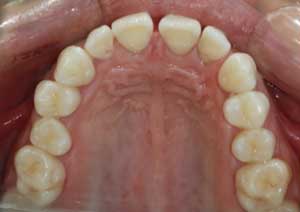

En orthodontie, une béance antérieure est une malocclusion caractérisée par l’absence de contact entre les incisives supérieures et inférieures lorsqu’on ferme les dents.

Traitement : Une ingression des molaires maxillaires avec une égression contrôlée du secteur antérieur a été réalisée à l’aide des arcs dits “Rocking Chair”, associés à des élastiques antérieurs portés de canine à canine, à droite et à gauche.

Cette mécanique permet de corriger la béance antérieure tout en conservant un contrôle précis de la position des dents antérieures et postérieures.

Avant